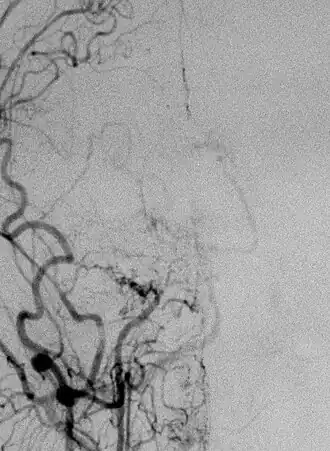

Боле́знь моямоя (от яп. もやもや — клуб дыма, туман) (БММ) — редкое хроническое прогрессирующее заболевание сосудов головного мозга, для которого характерно медленное (в течение месяцев и лет) сужение просвета внутричерепных сегментов внутренних сонных артерий (ВСА) и начальных отделов передних мозговых артерий и средних мозговых артерий вплоть до их окклюзии. Яркая отличительная черта заболевания — формирование сети коллатеральных сосудов на основании мозга, что на ангиограммах создает впечатление легкой дымки (G. Sébire и др., 2004)[2]. Именно этот признак в 1969 году дал современное название заболеванию: в переводе с японского «моямоя» обозначает «клуб дыма» (J. Suzuki и др., 1969)[3]. Первое описание БММ относится к 1957 году и принадлежит Takeuchi и Shimizu (K. Takeuchi и др., 1957) [4].

Диагностику заболевания строят исходя из клинической картины и дополнительных исследований. Наиболее информативны ангиография сосудов головного мозга, компьютерная томография, магнитно-резонансная томография, магнитно-резонансная ангиография, однофотонная эмиссионная компьютерная томография.

По Фукуи М. (1997)[8], радиологические критерии болезни следующие:

• наличие стеноза или окклюзии терминальных концов ВСА и проксимальных отделов передней и средней мозговых артерий;

• появление патологической сосудистой сети, видимой в области окклюзии;

• выявление при краниальной ангиографии признаков сосудистых изменений, типичных для БММ и носящих двусторонний характер.